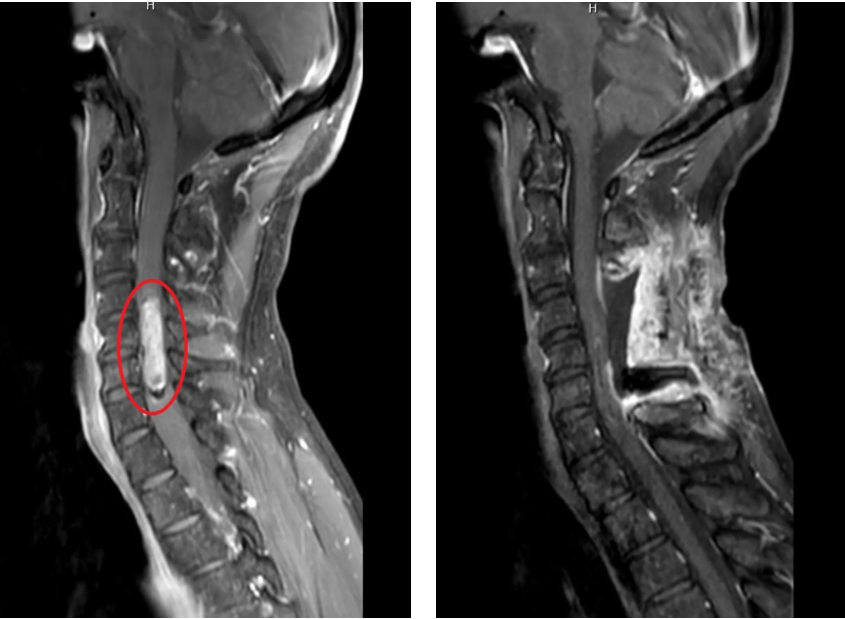

60 岁的田大叔被颈部疼痛伴四肢躯干麻木的症状困扰了 1 年多,并在短短一周内症状持续加重。在当地医院行颈部核磁检查提示脊髓占位,由于当地医疗条件局限,医生建议前往上级医院治疗。此时,肿瘤已经对颈髓造成明显挤压移位,若病情进一步发展,患者将面临截瘫的风险。

时间在紧张的氛围中悄然流逝,数小时后,最后一块肿瘤组织被成功分离。术后核磁共振显示肿瘤实现全切,病理报告进一步证实为相对良性的脊髓室管膜瘤 —— 完整切除,意味着治愈的曙光照进现实。

如今,定期回院复查的田大叔,望着屏幕上形态渐趋正常的脊髓,眼中满是劫后余生的欣慰。这场在毫米之间展开的生命博弈,既是医学技术的胜利,更是医者仁心的见证 —— 神经导航技术突破了传统手术的 「盲区」,医生们精益求精的执着则让 「生命禁区」 不再遥不可及。在医学科技与医者担当的双重护航下,曾经的 「禁区」 正被不断突破,那些关于 「治愈还是致残」 的焦虑,正被一个个成功故事悄然化解,新生的曙光正在跨越 「治愈或致残」 的鸿沟,照亮更多患者的康复之路。